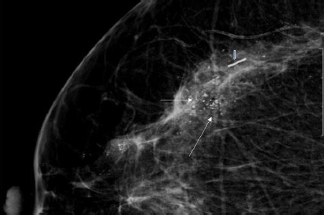

Coarse heterogeneous

These irregular calcifications are generally larger than pleomorphic calcifications measuring between 0.5mm-1mm; commonly seen in fibroadenomas, fibrosis or areas of trauma eventually becoming dystrophic calcifications. When bilateral, groups of these calcifications, can be categorized as benign. When a single group of these calcifications is seen, they can be associated with malignancy and have a Positive predictive value of <15%, and hence are categorized as BIRADS 4b [5]; (Figure 14).

Figure 14:RCC zoomed in view of a 51-year-old woman with coarse heterogeneous calcifications (long arrows). A metallic marker is also seen (short arrow). Image Courtesy: HCG hospitals, Bangalore.